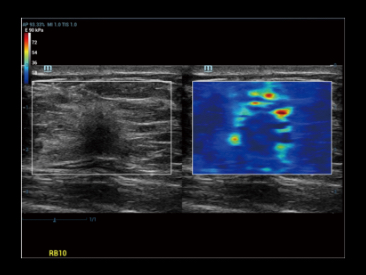

ZST+

Технология зонного сканирования.